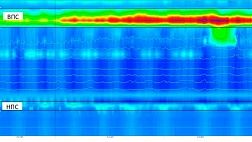

Эластография при эндосонографии (ЭУС или эндоУЗИ)

Эластография (эластосонография) – метод виртуальной пальпации (технология улучшенной визуализации при ЭУС диагностике), позволяющий дифференцировать злокачественные и доброкачественные поражения лимфоузлов. Основана на принципе, что более мягкие ткани при сжатии легче деформируются, это позволяет объективно оценить консистенцию ткани, показать различия в плотности между нормальными и патологически измененными тканями.